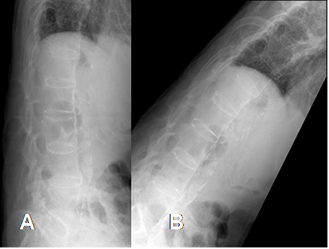

Fig 56 E. Espondilitis anquilosante.

A: Rx lateral. Sindesmofitos, con el aspecto de columna en bambú.

B: Gran rigidez y poca movilización, en la proyección de flexión.